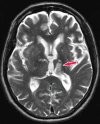

Neurodegenerative diseases are a devastating group of disorders that can be difficult to accurately diagnose. Although these disorders are difficult to manage owing to relatively limited treatment options, an early and correct diagnosis can help with managing symptoms and coping with the later stages of these disease processes. Both anatomic structural imaging and physiologic molecular imaging have evolved to a state in which these neurodegenerative processes can be identified relatively early with high accuracy. To determine the underlying disease, the radiologist should understand the different distributions and pathophysiologic processes involved. High-spatial-resolution MRI allows detection of subtle morphologic changes, as well as potential complications and alternate diagnoses, while molecular imaging allows visualization of altered function or abnormal increased or decreased concentration of disease-specific markers. These methodologies are complementary. Appropriate workup and interpretation of diagnostic studies require an integrated, multimodality, multidisciplinary approach. This article reviews the protocols and findings at MRI and nuclear medicine imaging, including with the use of flurodeoxyglucose, amyloid tracers, and dopaminergic transporter imaging (ioflupane). The pathophysiology of some of the major neurodegenerative processes and their clinical presentations are also reviewed; this information is critical to understand how these imaging modalities work, and it aids in the integration of clinical data to help synthesize a final diagnosis. Radiologists and nuclear medicine physicians aiming to include the evaluation of neurodegenerative diseases in their practice should be aware of and familiar with the multiple imaging modalities available and how using these modalities is essential in the multidisciplinary management of patients with neurodegenerative diseases.©RSNA, 2020.